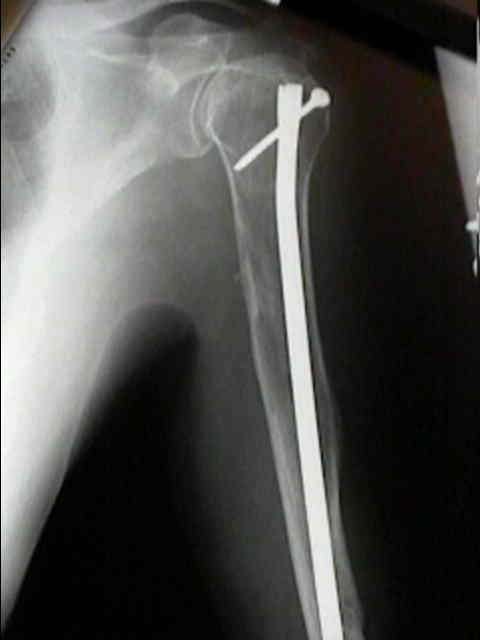

Hallazgo radiológico característico

- Enfermedad ósea lítica: activación osteoclástica e inhibición osteoblástica → lesiones “en sacabocado”, fracturas y dolor.

- Dolor óseo (columna, costillas, pelvis), fracturas por fragilidad, pérdida de altura vertebral.

- Radiología/TC: lesiones osteolíticas “en sacabocado”, osteopenia difusa, fracturas vertebrales.

- Cirugía ortopédica: fracturas patológicas, inestabilidad, lesiones de alto riesgo mecánico; planificación con imagen.